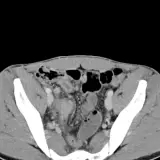

Casos totalmente interactivos con las herramientas que esperaría de un PACS: scroll, ventana, zoom, pan, mediciones, ROI y modo de pantalla completa.

• Anotaciones enlazadas

Anotaciones extensas resaltan los hallazgos clave directamente sobre los casos. Haga clic en los hallazgos enlazados dentro de la descripción del caso para saltar a su ubicación exacta en el estudio.

Desplace, arrastre, ajuste ventana y amplíe como en una estación PACS de trabajo

Aprenda con eficiencia gracias a hallazgos de imagen anotados e ilustraciones